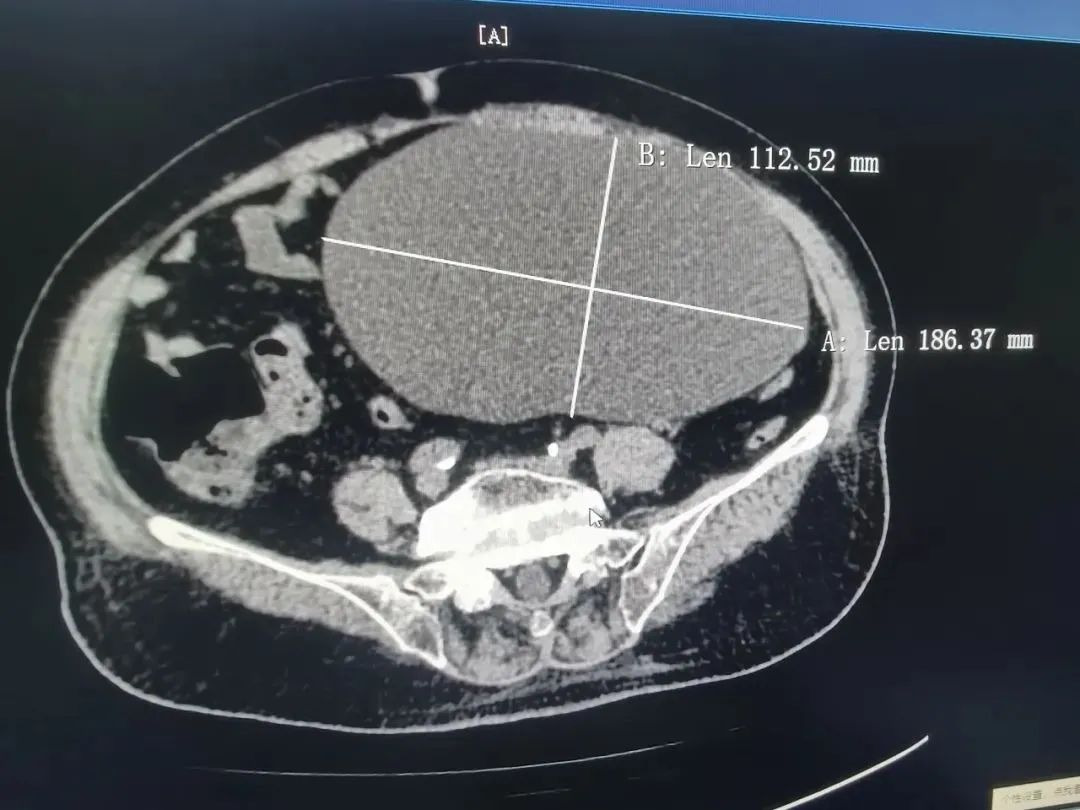

18厘米巨大肿瘤占满83岁阿婆盆腔,多学科团队紧密协作联合"拆弹"